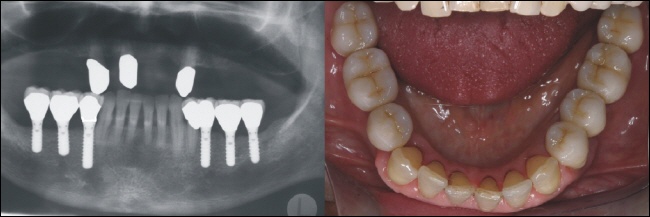

Zum Ersatz der fehlenden Zähne wurden auf jeder Seite drei Implantate eingebracht. Auf dem rechten Bild sieht man die Verschlusskappen der sechs eingebrachten Implantate. |